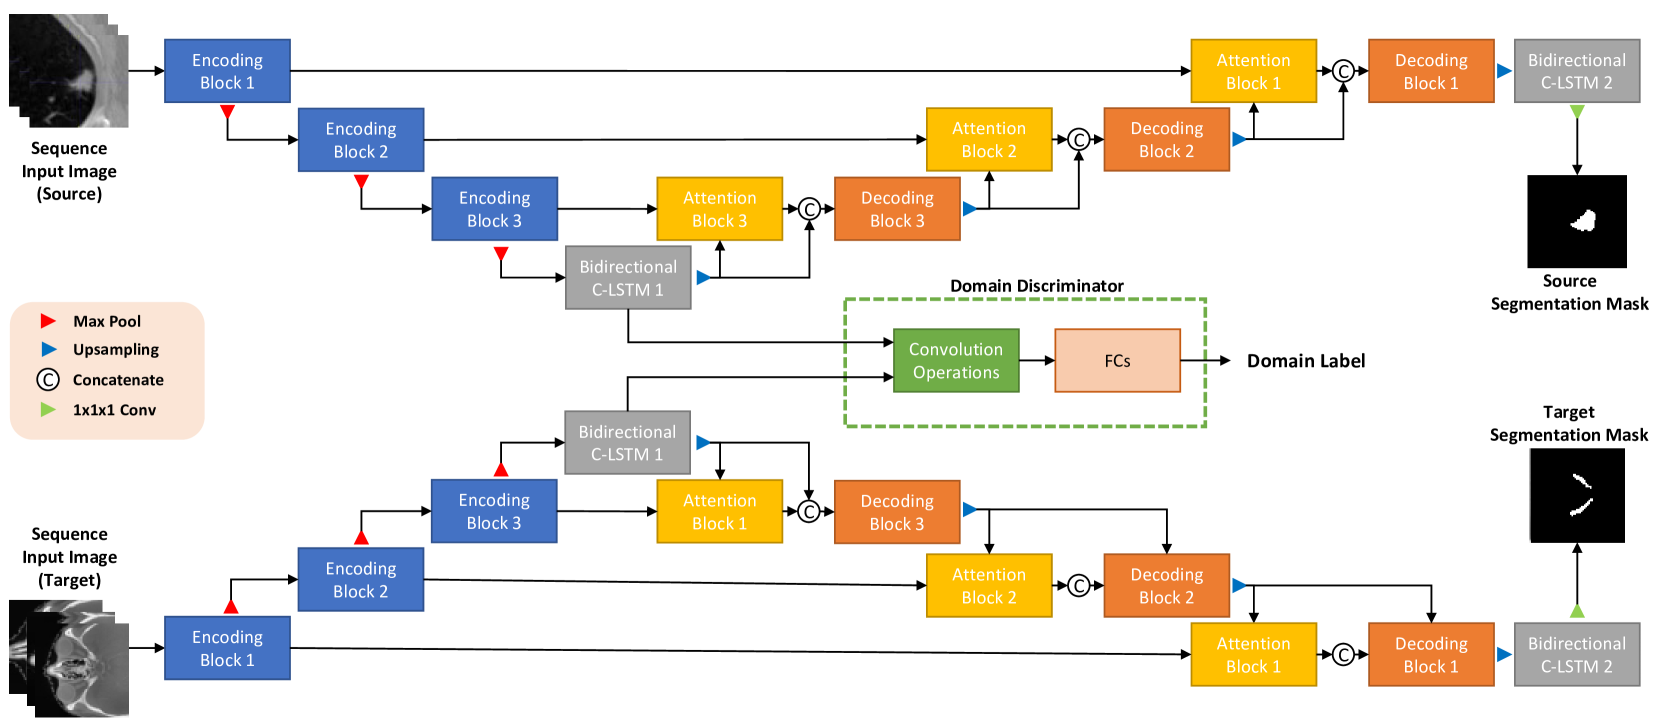

Furthermore, we applied the domain adaptation approach to the feature extraction process, using an adversarial learning framework. Fig. 1 displays the overall procedure of the proposed framework.

To alleviate the problem of small annotated datasets, we applied the domain adaption technique to SEQ-UNET.The feature representation learning process extracted features that were more invariant to differences between the two domains, by employing a domain discriminator to distinguish between the source and target features from the encoder, in the U-Net architecture. Fig. 1 presents the overall network architecture of the proposed framework with the domain adaptation.

There are four types of network structures in the proposed framework: 1) a feature extractor inclusive of encoding blocks in the U-Net structure, and a bidirectional C-LSTM, 2) attention gates, 3) a reconstructor, including decoding blocks in the U-Net structure and a bidirectional C-LSTM, and 4) a domain discriminator. The domain discriminator was appended to the end of the encoder with the bidirectional C-LSTM layer, with the most complex feature. We used adversarial learning that had an objective function of the min-max game between the feature extractor and the domain discriminator. The feature extractor extracted domain invariant features to trick the domain discriminator, while the domain discriminator was trained to distinguish between features extracted from the source and target domain data. The detailed structure of the proposed domain adaptation networks is also shown in Table I. Furthermore, we integrated a dice loss function into the overall loss function, for the segmentation loss between the segmentation mask and the result from the reconstructor. This was done because the data ratio between the background and foreground was severely imbalanced, and the dice score could effectively mitigate the problem of class imbalance. The objective functions of the proposed method are defined as follows: